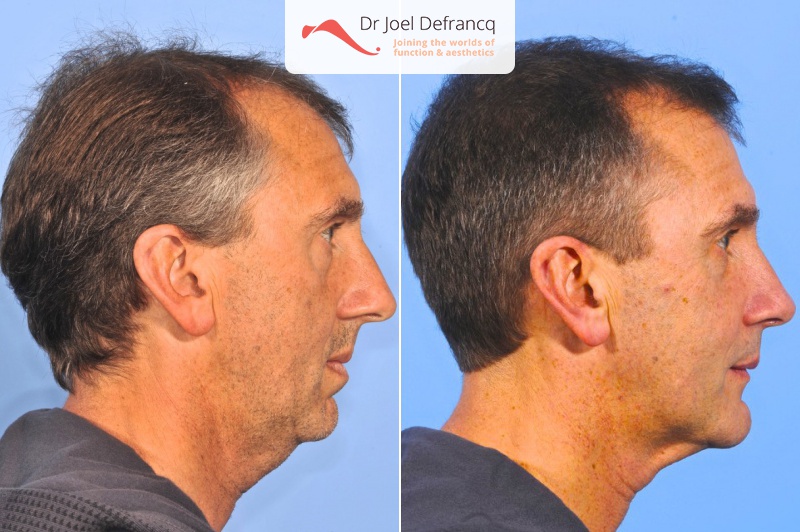

Jhonny: Kleine onderkaak, te kleine en te korte bovenkaak,

Diagnose van het gezicht

- Te kleine onderkaak (Overbeet)

- Te kleine bovenkaak

- Te kort gezicht

- Te korte bovenkaak

- Gekanteld beetvlak

Kaakchirurgie

- Verlenging onderkaak (BSSO)

- Verlenging bovenkaak (Le Fort I)

- Kinchirurgie

- Verbreden bovenkaak (Smile distractor)

Esthetische chirurgie

- Jukbeen augmentatie